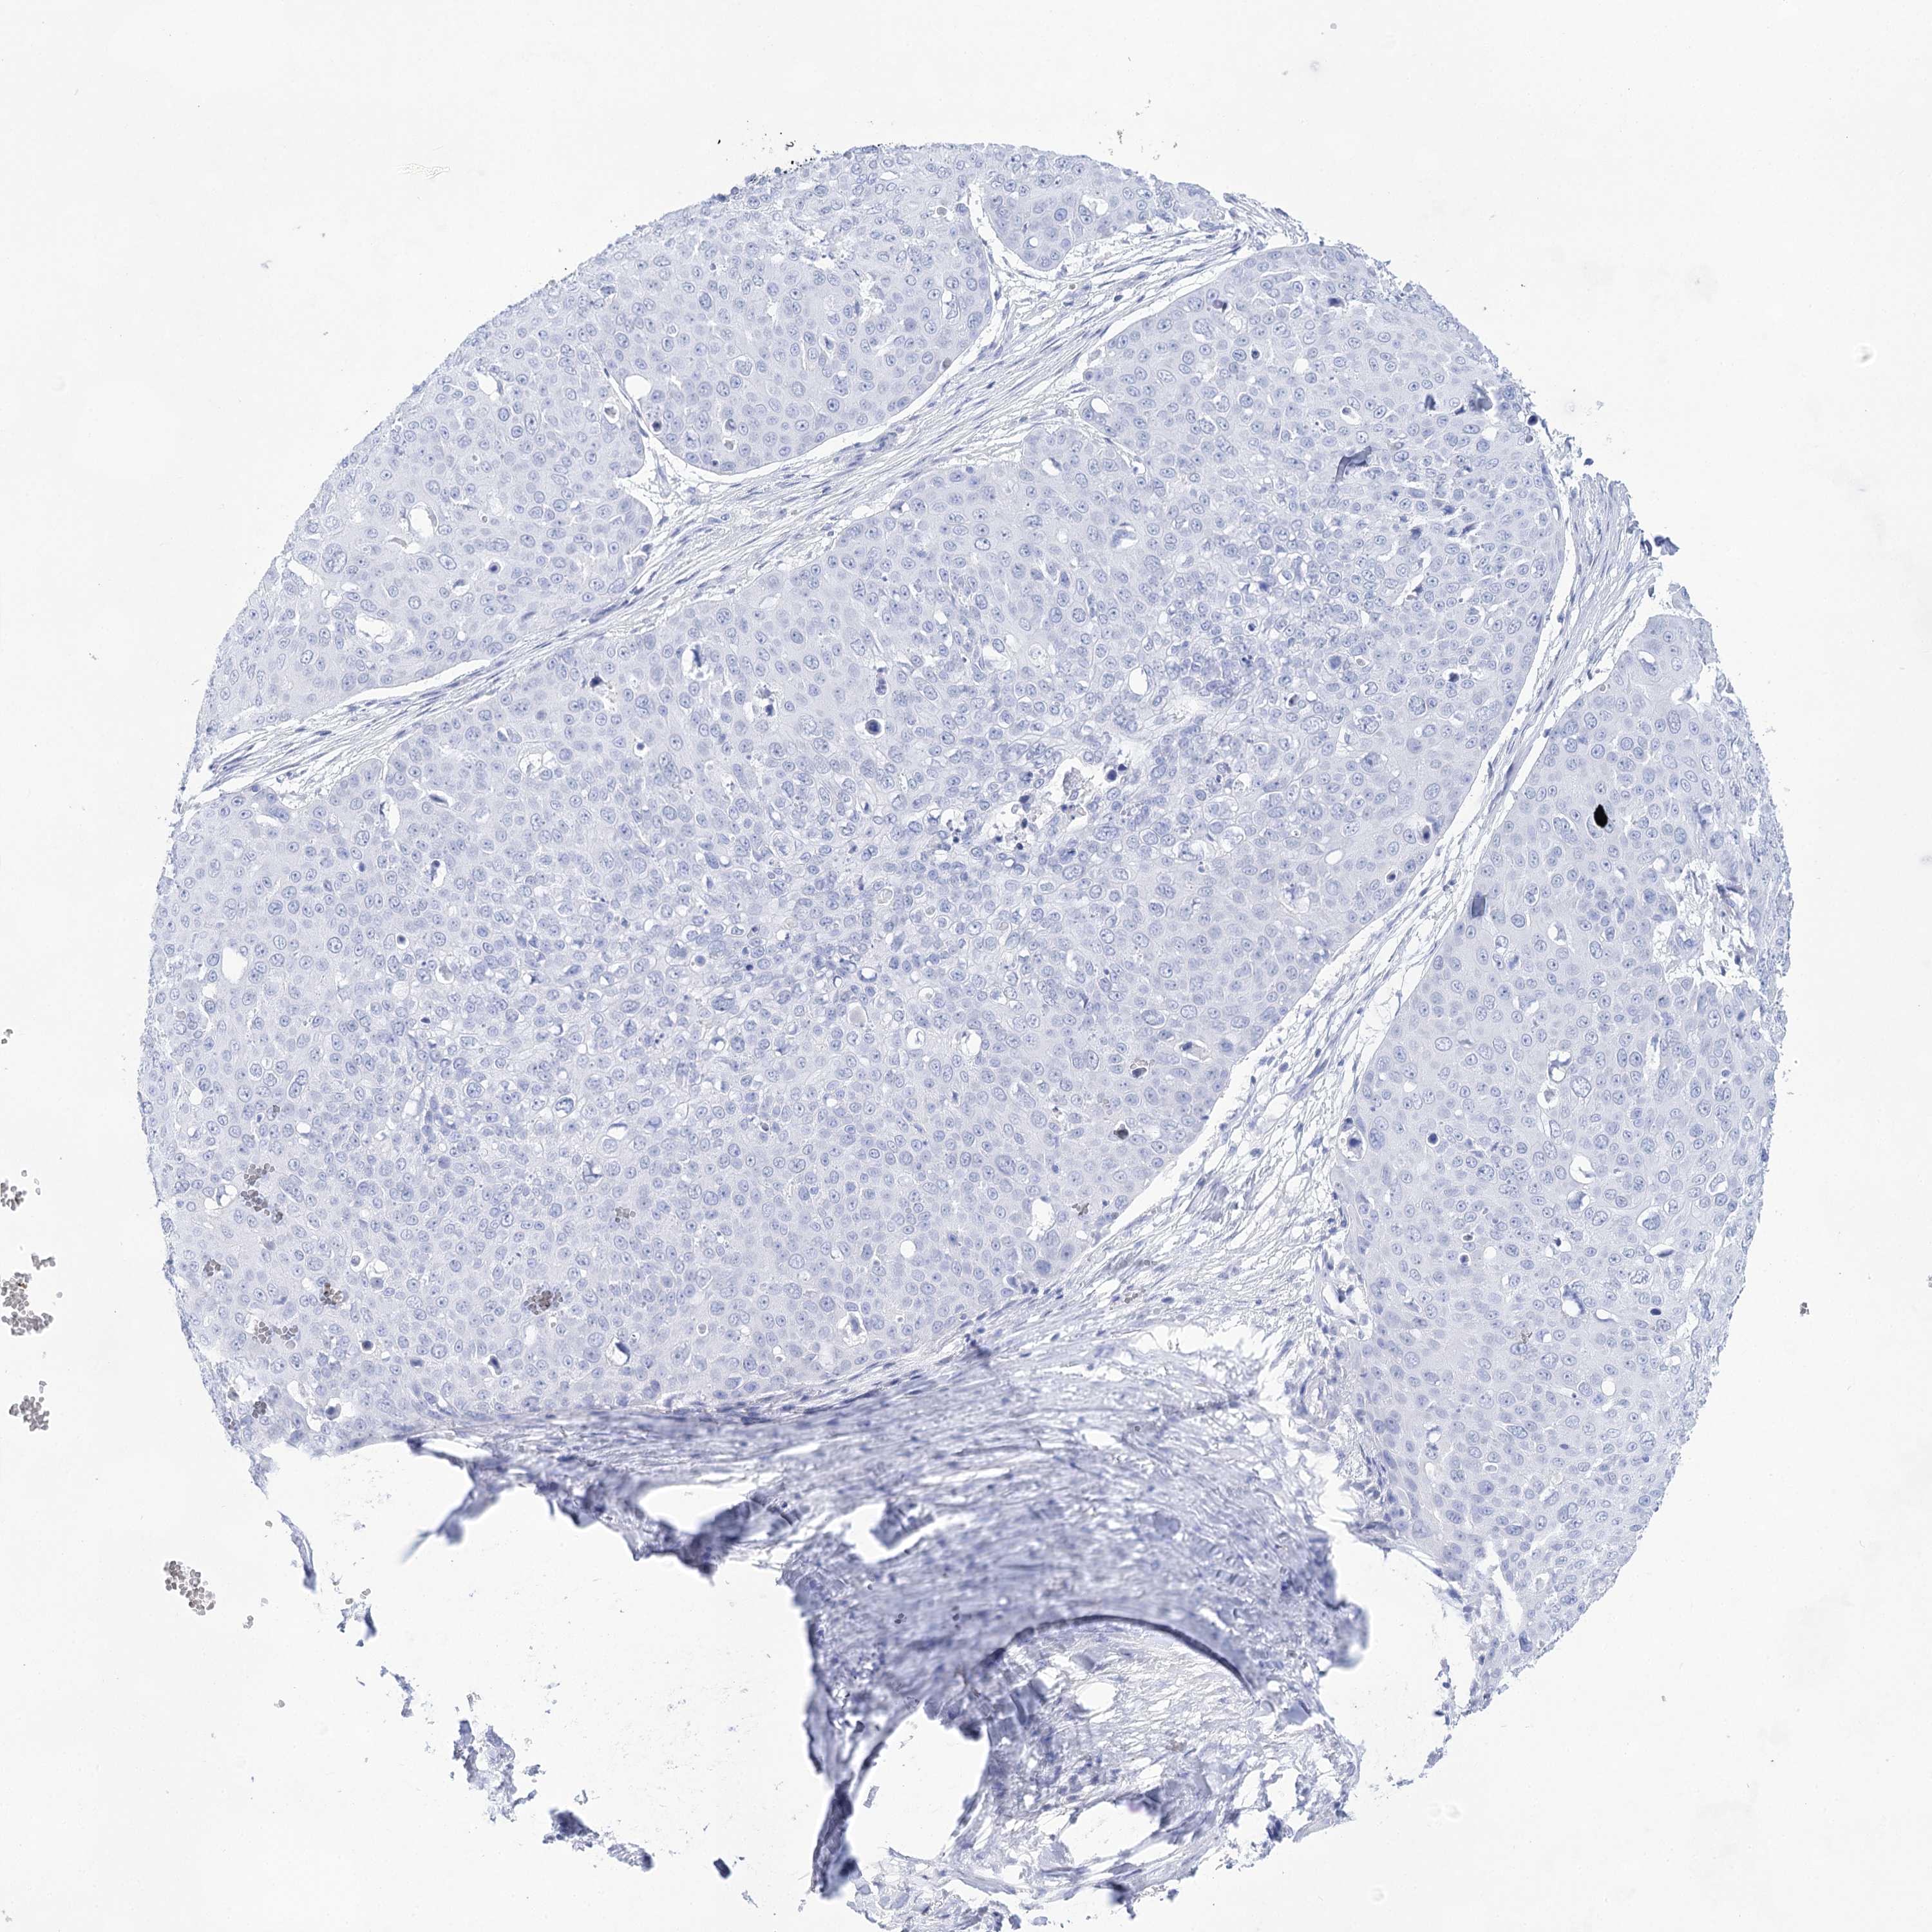

CANCER SKIN CANCER Show tissue menu

Basal cell and squamous cell cancer

SKIN CANCER - Protein expressioni

A mouse-over function shows sample information and annotation data. Click on an image to view it in a full screen mode. Samples can be filtered based on level of antibody staining by selecting one or several of the following categories: high, medium, low and not detected. The assay and annotation is described here.

Each image is clickable and will lead to virtual microscopy that enables deeper exploration of all samples and also displays staining intensity scores, fraction scores and subcellular localization as well as patient and tissue information for each sample.

Antibody HPA029855

Antibody HPA029856

Antibody CAB026343

Basal cell carcinoma

Squamous cell carcinoma, NOS

Squamous cell carcinoma, metastatic, NOS